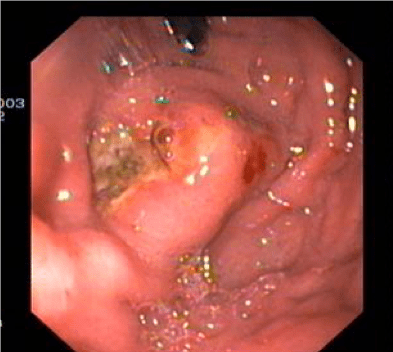

- Endotherapy of ulcers